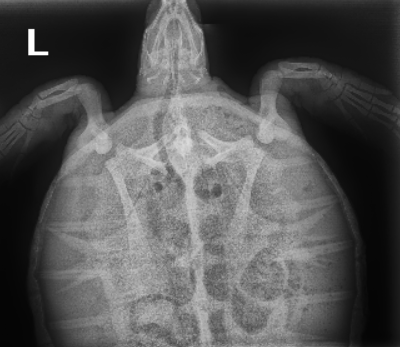

6.65Kg Atlantic Green Sea Turtle

Older lesion on the dorsal region of the carapace, small abrasion to the head, notches missing from both front flippers and abrasions to the rear flippers, abrasion to the top of the head.